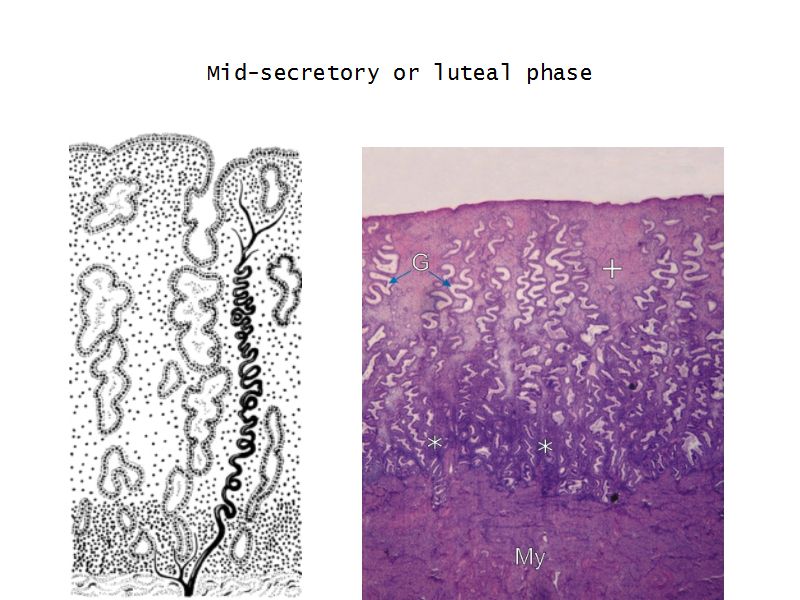

Menstrual cycle

- Luteal phase

Luteal phase

- Thickening endometrium

- Edema

- Endometrial gland secretion

- Glands

- Glandular cells at apex

- Basal accumulation glycogen

- Helical arteries reach superficial regions